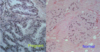

What are the differences between these two images?

Left is breast tissued during pregnancy –> larger lobules + ducts

Right is normal (unstimulated) breast tissue –> lobules and ducts much smaller